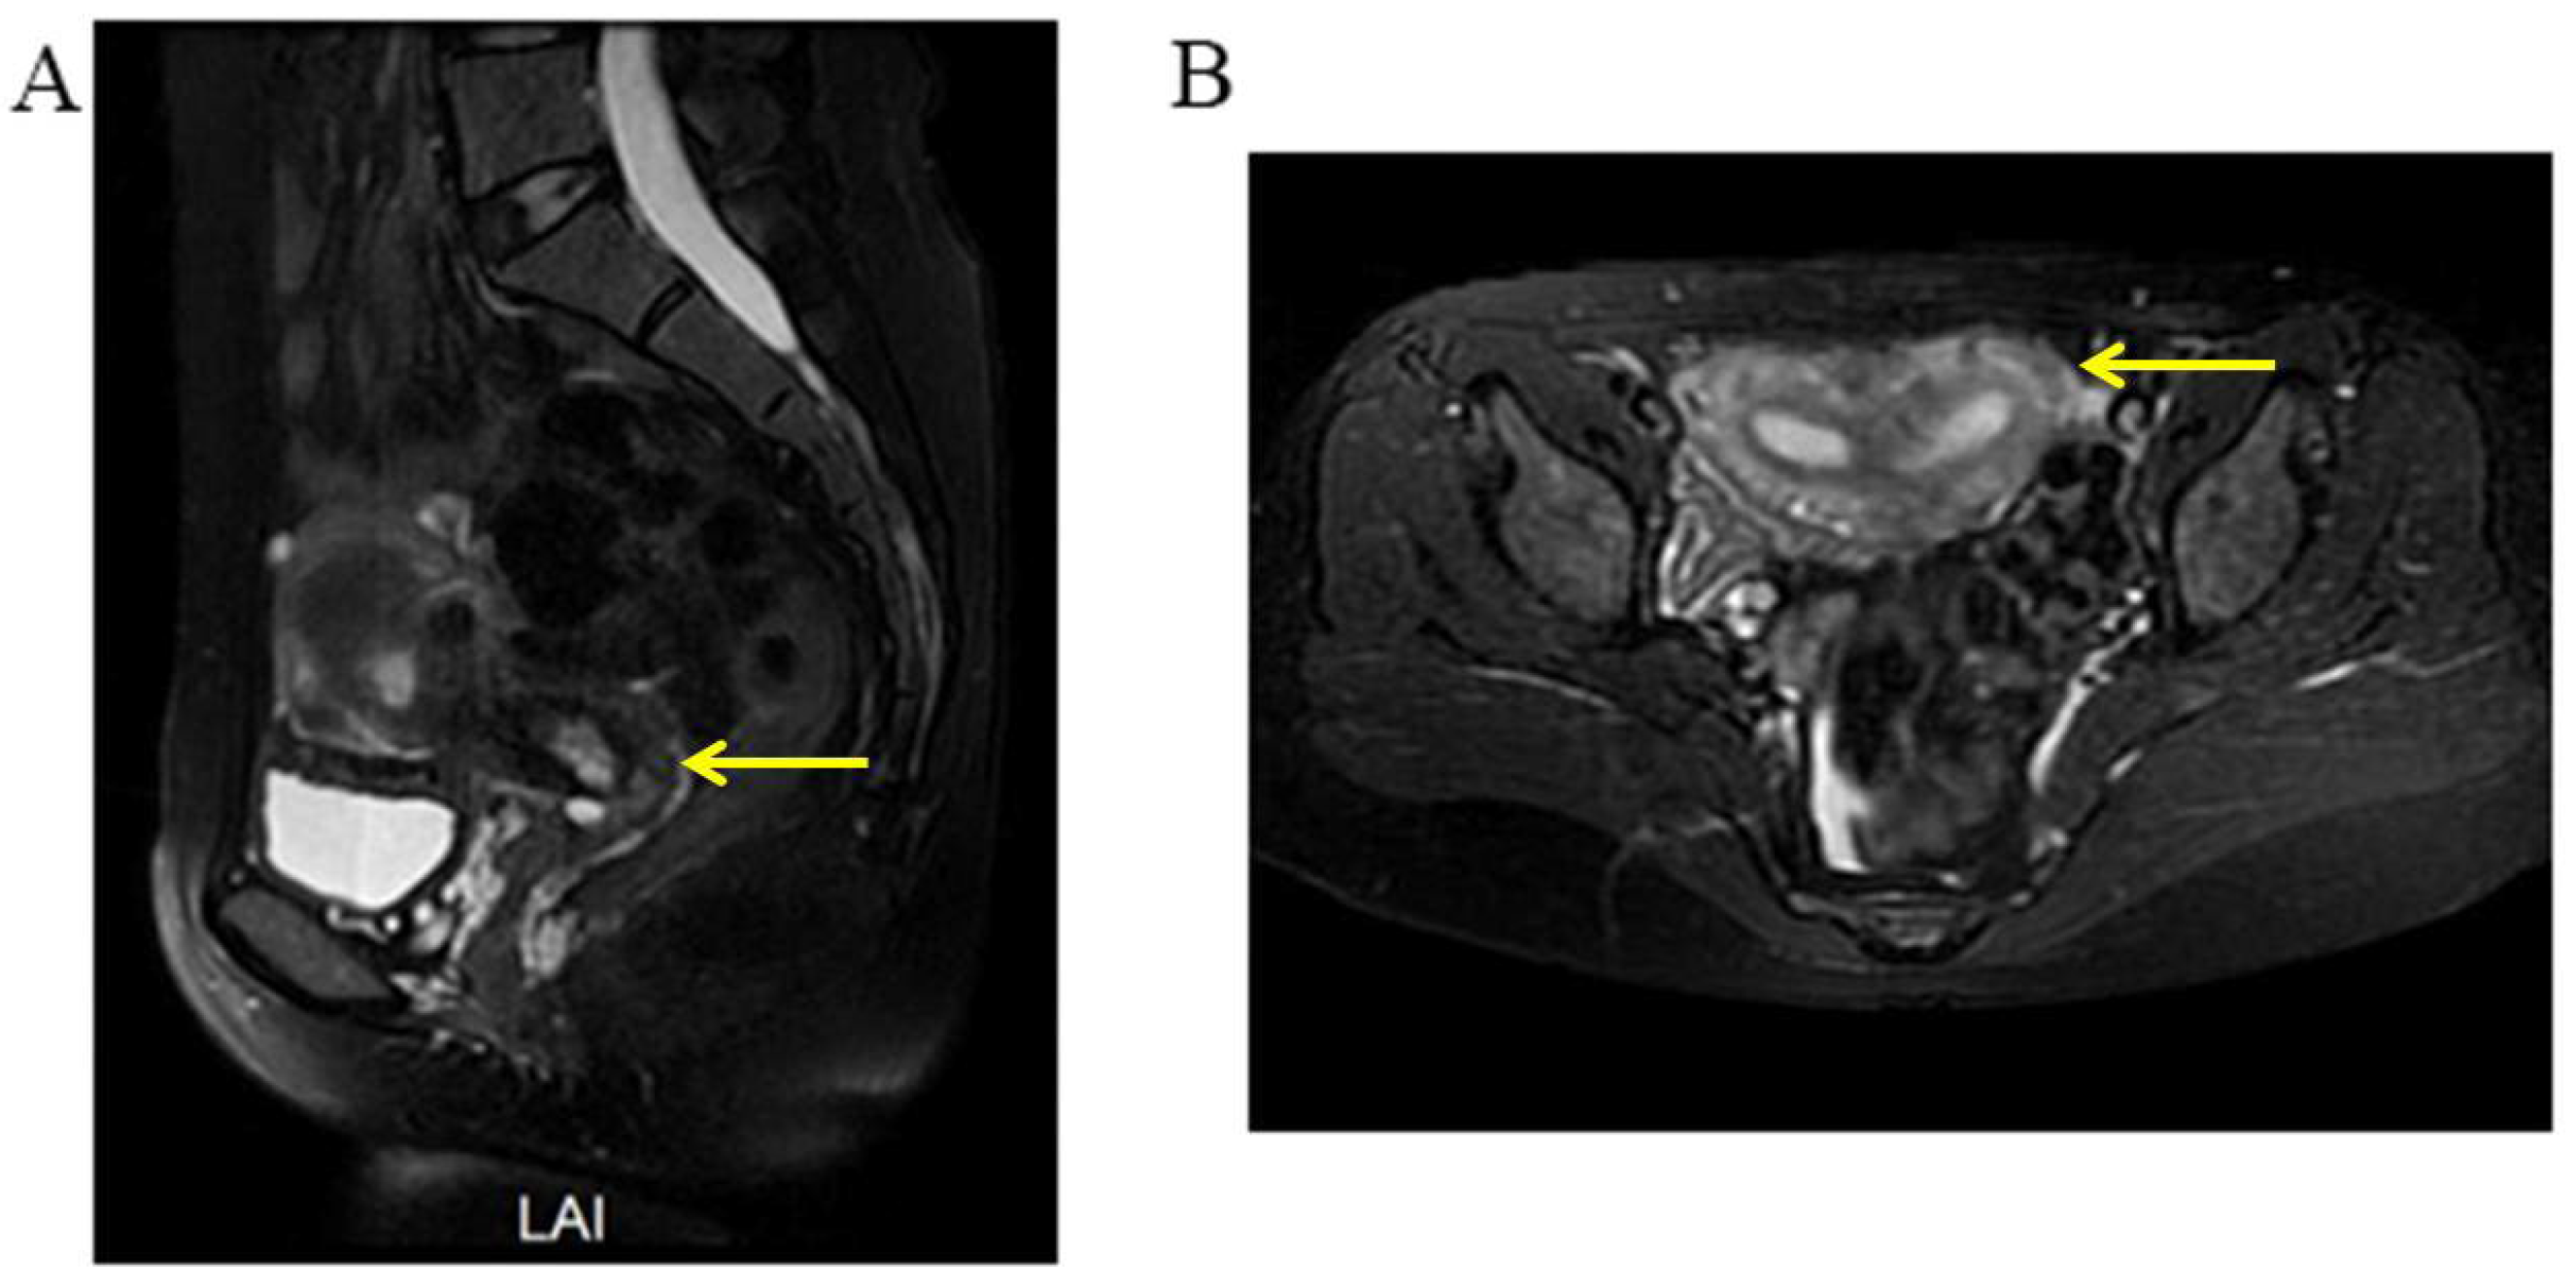

A three-dimensional transvaginal ultrasound revealed adenomyosis and a septate uterus (Figure 1). Two cystic masses with thick internal fluid measuring 3.7 × 4.2 × 2.7 cm (Figure 1A) and 7.5 × 3.1 × 2.1 cm (Figure 1B) were seen on the right side of the uterus, respectively. These cystic masses were considered to be a hydroureter with vaginal fistula. A urinary tract ultrasound revealed the absence of a right kidney, as well as a dilated right ureter measuring 11.1 × 1.8 cm with an ectopic opening into the right vagina (Figure 2A). A computed tomography urography (CTU) revealed the absence of the right kidney (Figure 2B). A pelvic MRI showed a cystic mass considered to be a mesonephric cyst on the right side of the pelvis, bladder, and urethra (Figure 3A). A complete septate uterus with multiple fibroids was also found (Figure 3B). The creatinine concentration of the fluid inside the pelvic cyst was measured to be 157 nmol/L via transvaginal aspiration (Figure 4).

Figure 3.

Selected MRI images of the pelvis. (A) Pelvic MRI showed a fluid-filled cyst (yellow arrow) along the right side of the pelvis, bladder, and urethra (mesonephric remnants). (B) Pelvic MRI showed a complete septate uterus with multiple fibroids (yellow arrow).